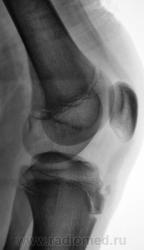

Пациент направлен на рентгенографию коленного сустава с диагнозом - Болезнь Осгут - Шлаттера.

фрагментация бугристости Б\Б кости

Болезнь Осгут - Шлаттера, как-то не вдохновляет. Более склонен к консоидирующемуся отрывному перелому бугристости б/берцовой кости.

Более склонен к варианту окостенения, хотя травматический генез, как и асептический некроз (абсолютно согласен с Максималистом - при наличии клиники и анамнеза) с повестки дня окончательно, до выяснения оных, не снимаются.

Уважаемые коллеги! На мой взгляд, выявленное на рентгенограмме, образование костной плотности, с четкими, ровными контурами, однородное по своей структуре отношения с бугристости большеберцовой кости не имеет. Хотелось бы знать возраст пациента, его анамнез (спорт, травмы области коленного сустава). Больше похоже на обызвествления собственной связки надколенника. Дополнил бы УЗИ коленного сустава.